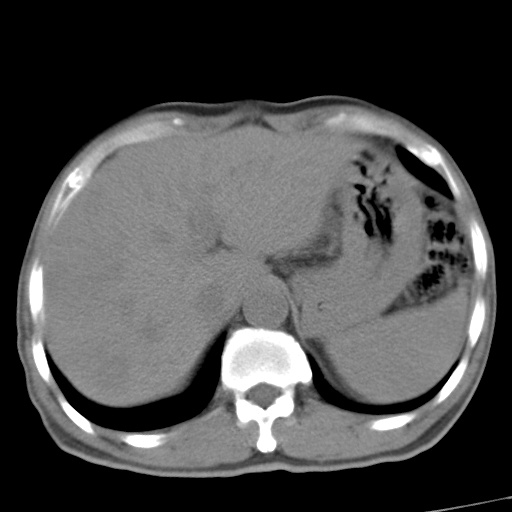

标题: CT17975:请求会诊。男、57岁。上腹部胀痛2天。临床诊断:糜 [打印本页]

标题: CT17975:请求会诊。男、57岁。上腹部胀痛2天。临床诊断:糜

肝脏多发类圆形低密度影,考虑肝脏转移瘤,肝胃韧带一淋巴结肿大,原发?胃癌?

考虑胃癌肝脏转移可能性大。

支持胃癌肝转移